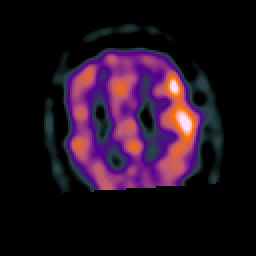

Subacute Stroke, overlay -- Slice #19

[Home][Help][Clinical] Slice 19

Click on sagittal image to select slice. Click on thin tickmark to change timepoint, or thick tickmark for overlay.